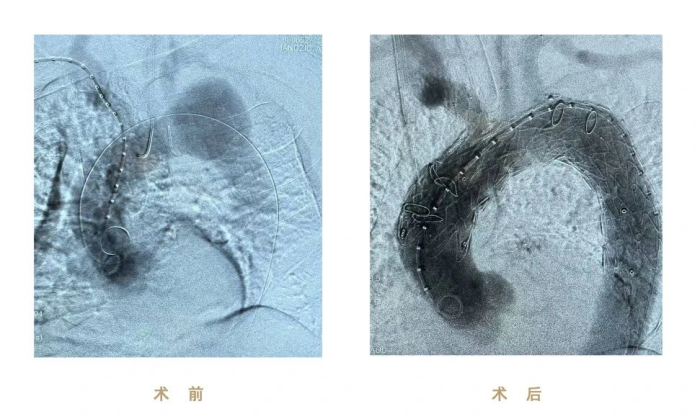

图片 2.png

(图:术前、术后影像)

本次手术使用先健CS一体式弓部三分支重建系统进行腔内修复,逐次完成通路建立、CS主体支架植入及精准释放、弓上三分支(无名动脉、左颈总动脉、左锁骨下动脉)依次超选及分支支架植入,全程造影显示支架形态良好、无移位及内漏、三分支血流通畅,达到理想的隔绝与血供重建效果